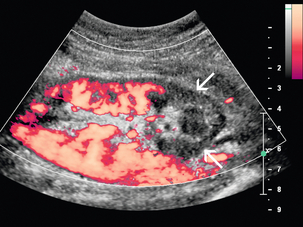

Артериовенозная фистула в нативной почке встречается редко, за исключением случаев предшествующей биопсии почки, и ее нельзя заподозрить при сонографии, если не проводится цветная или энергетическая допплерография. Цветной или энергетический допплер обычно показывает большое извилистое скопление сосудов. Спектральные допплеровские сигналы почечных артерий, питающих фистулу, покажут высокую скорость и низкое сопротивление ( рис. 9-19 ). Основная почечная вена может быть расширена, а в венах вблизи фистулы могут обнаруживаться артериализованные волны ( рис. 9-20 ).

РИСУНОК 9-20. Артериовенозная фистула. (А) Спектральная допплерография демонстрирует артериализованный венозный поток с высокими скоростями и низким сопротивлением. (B) КТ-ангиография показывает раннее усиление правой почечной вены (стрелка) по сравнению с левой почечной веной.